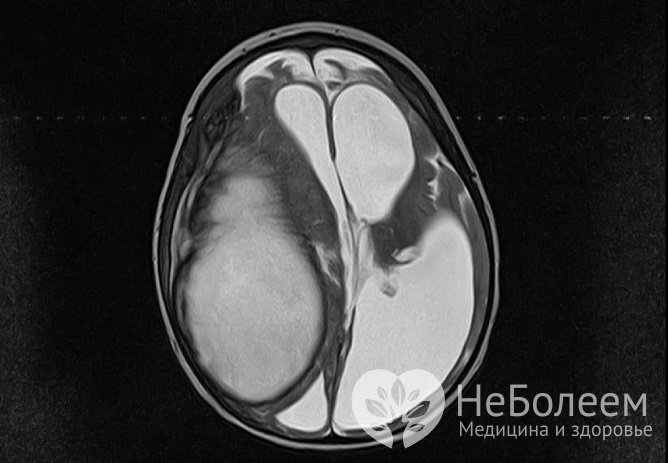

Абсцесс головного мозга – это локальное образование инфекционной природы, представляющее собой скопление гноя, изолированного от здоровых тканей мозга твердой соединительно-тканной капсулой. Составляет не более 1-2% от всех внутричерепных образований. Может встречаться в любом возрасте, но наиболее часто возникает у людей за 40. Болеют чаще мужчины.